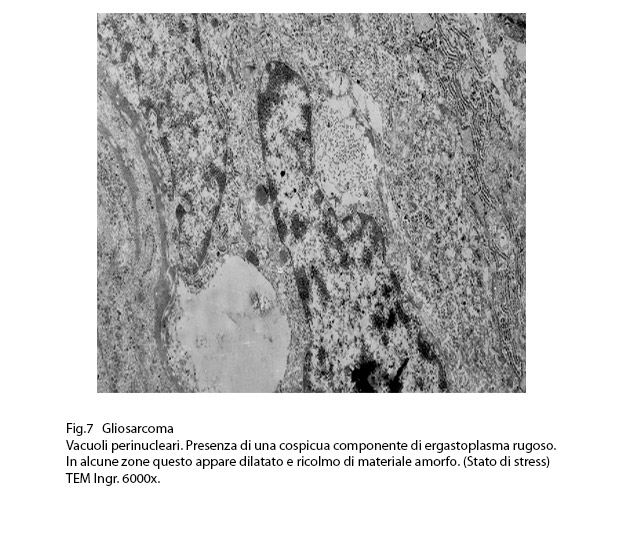

Fig.7

ERGASTOPLASMA

In diverse condizioni di patologia (malattie neurodegenerative, diabete, disordini metabolici, stress ossidativi, infezioni, flogosi,etc.) e tra queste anche nelle neoplasie maligne si può riscontrare l’ergastoplasma in condizioni di stress. (Genes Cancer 2010; 1:764-778) (Cell Biol. 2012; 197: 857-867)

Al microscopio elettronico l’ergastoplasma in stato di stress appare con cisterne dilatate e ricolme di materiale amorfo, debolmente elettropaco.

Questo materiale è costituito da proteine non correttamente ripiegate ed assemblate e pertanto non trasportabili e non utilizzabili e di conseguenza possono subire un processo di degradazione (ERAD= ER- Associated Degradation).

Nelle situazioni di stress temporaneo si ha un ripristino dell’omeostasi dell’ergastoplasma mediante il sistema UPR (Unfolded Protein Response); diversamente, se lo stato di stress dovesse prolungarsi (come si riscontra nelle cellule neoplastiche) si ha una situazione di stress estesa all’intera cellula,con successiva attivazione di un processo di autofagia e infine con l’instaurarsi di un processo di morte cellulare (Am J. Pathol. 2007; 171: 513-24) (FEBS 2016; 283: 498-509).

Anche nelle cellule dei gliosarcomi quì rivisitati, si repertano disfunzioni ergastoplasmatiche; infatti si evidenziano tratti della rete ergastoplasmatiche con cisterne dilatate e ricolme di materiale amorfo, debolmente elettropaco. In un minor numero di cellule questa disfunzione si appalesa sotto forma di fasci iperdensi di sub strutture ergastoplasmatiche variamente orientate,spesso con cisterne ectasiche e occupanti una ampia area del citoplasma.